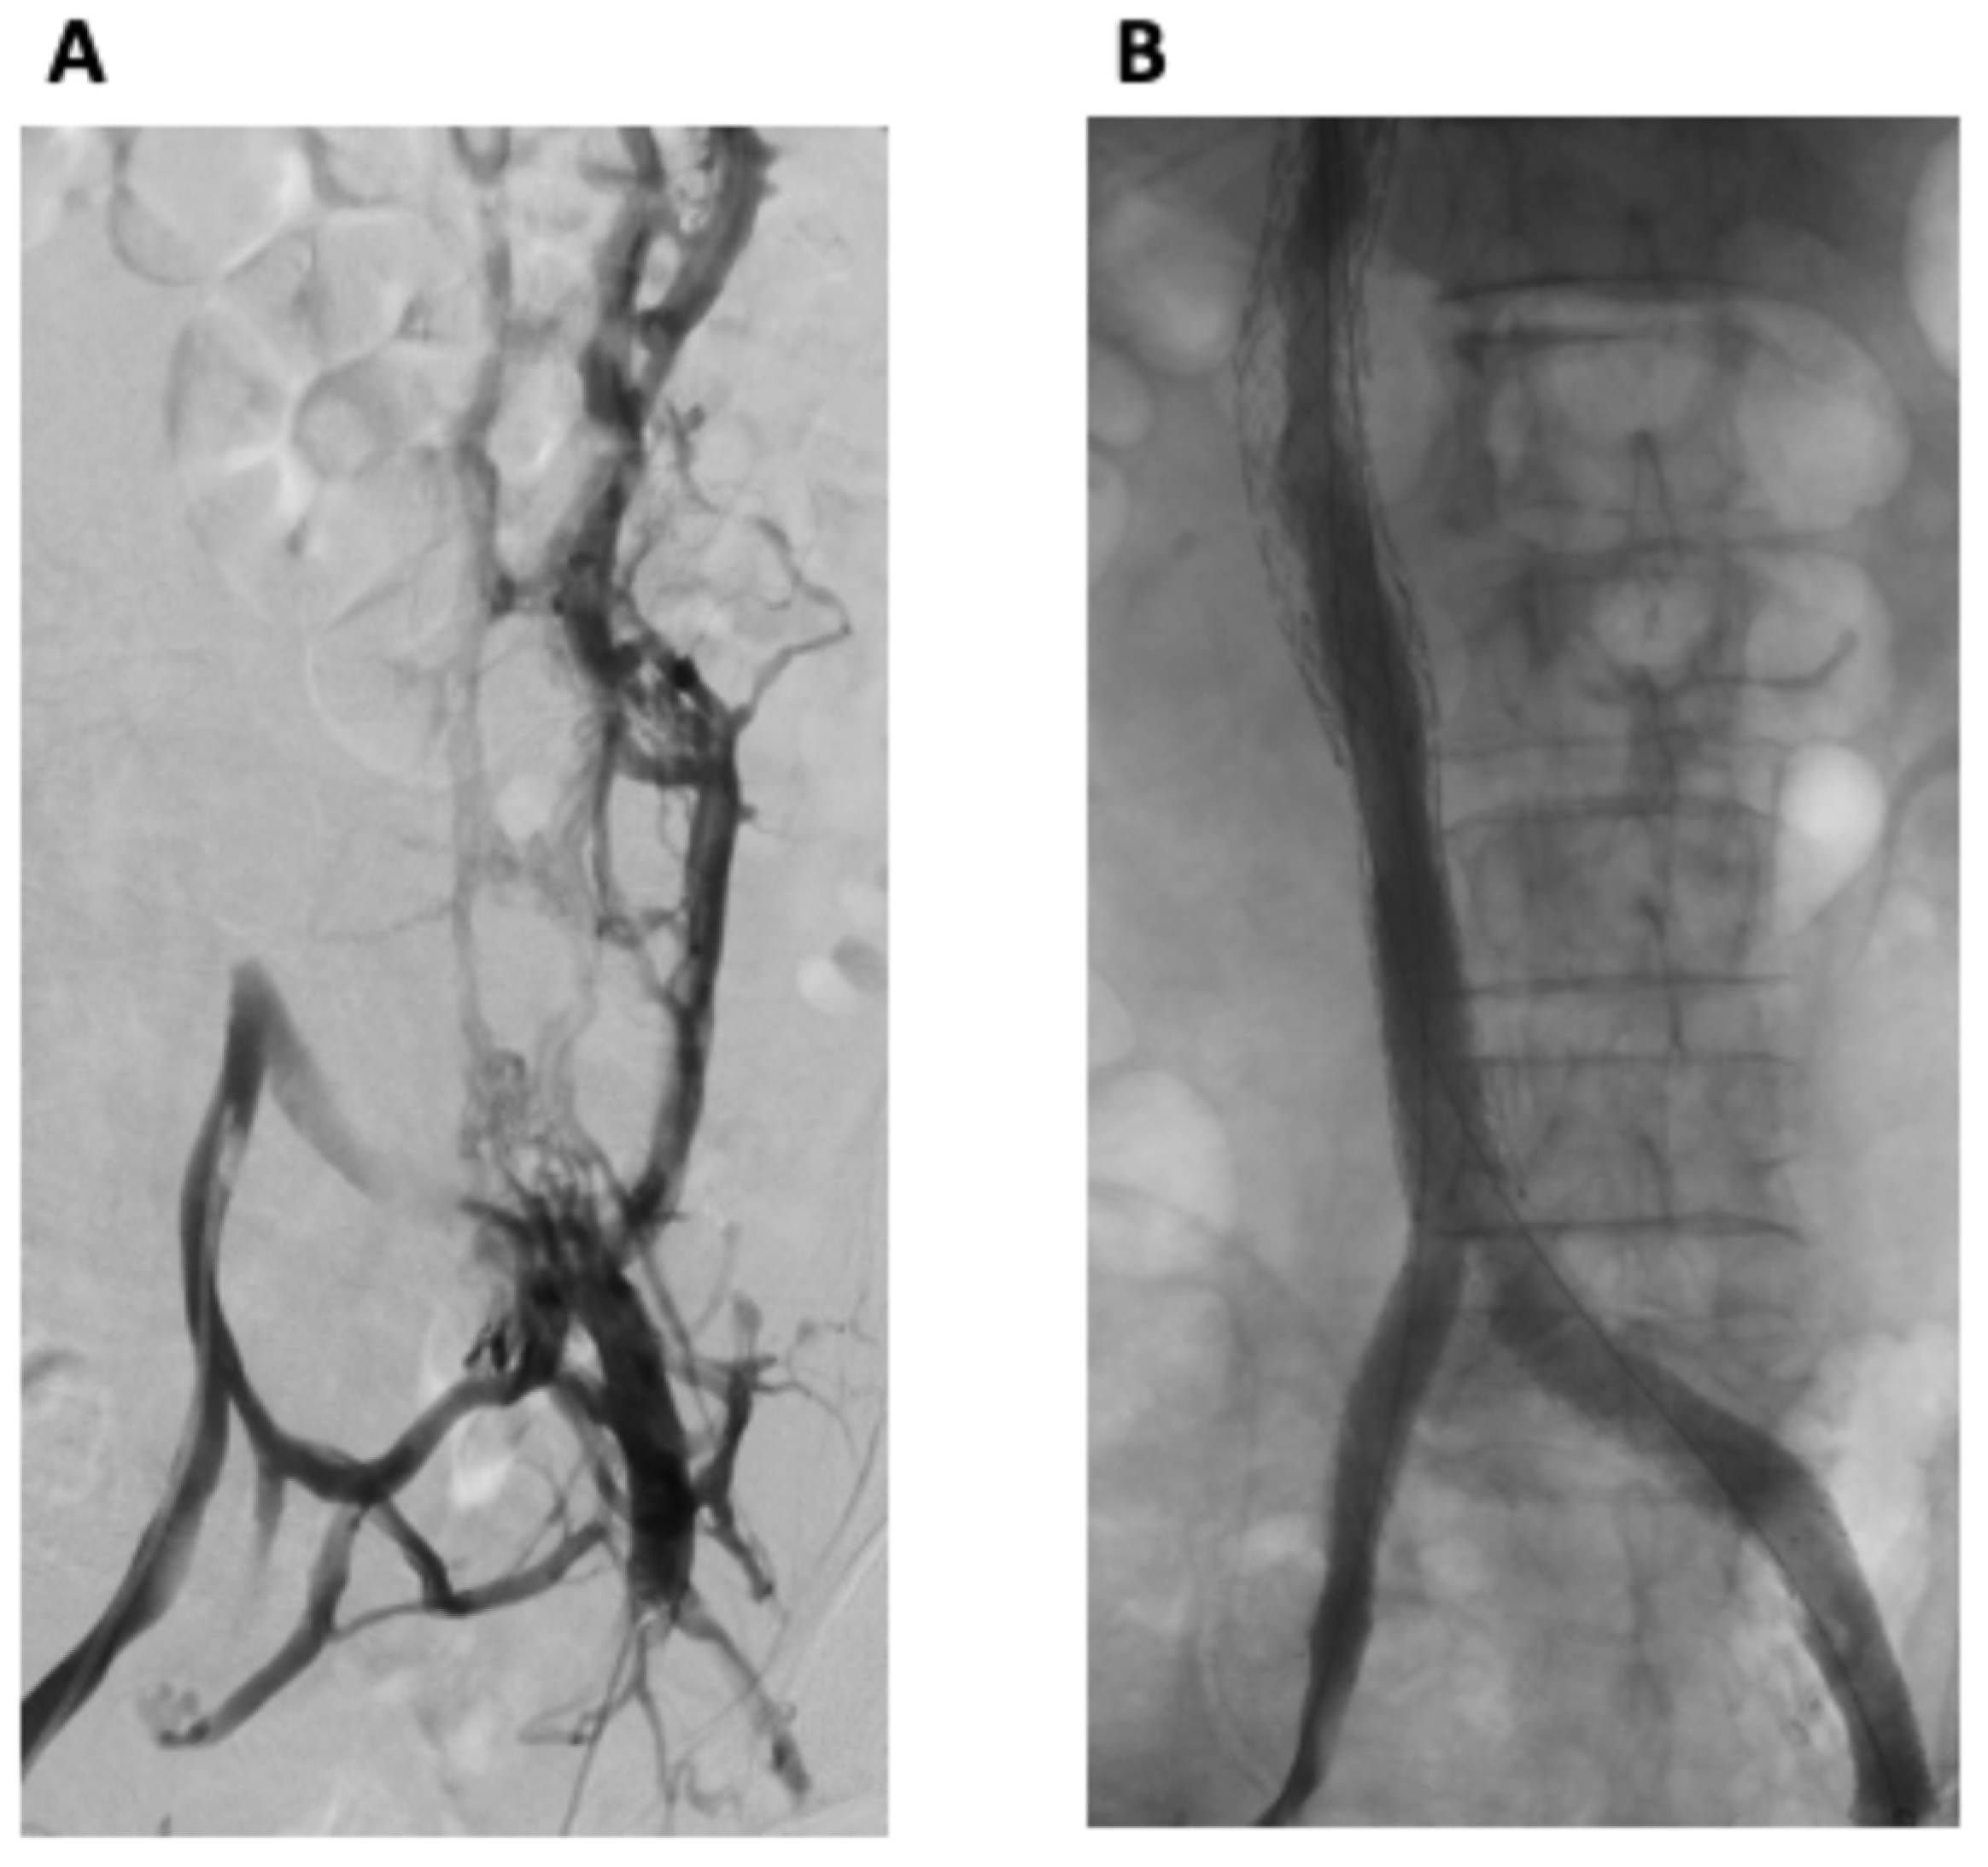

Total Iliocaval Reconstruction in a Complex Palliative Patient with Malignant Inferior Vena Cava Syndrome

Lofroth, J.; Pourghadiri, A.; Hadjivassiliou, A.; Heran, M.; Legiehn, G.; Ho, S.; Dhatt, R. Total Iliocaval Reconstruction in a Complex Palliative Patient with Malignant Inferior Vena Cava Syndrome. Curr. Oncol. 2024, 31, 3978-3984. https://doi.org/10.3390/curroncol31070294